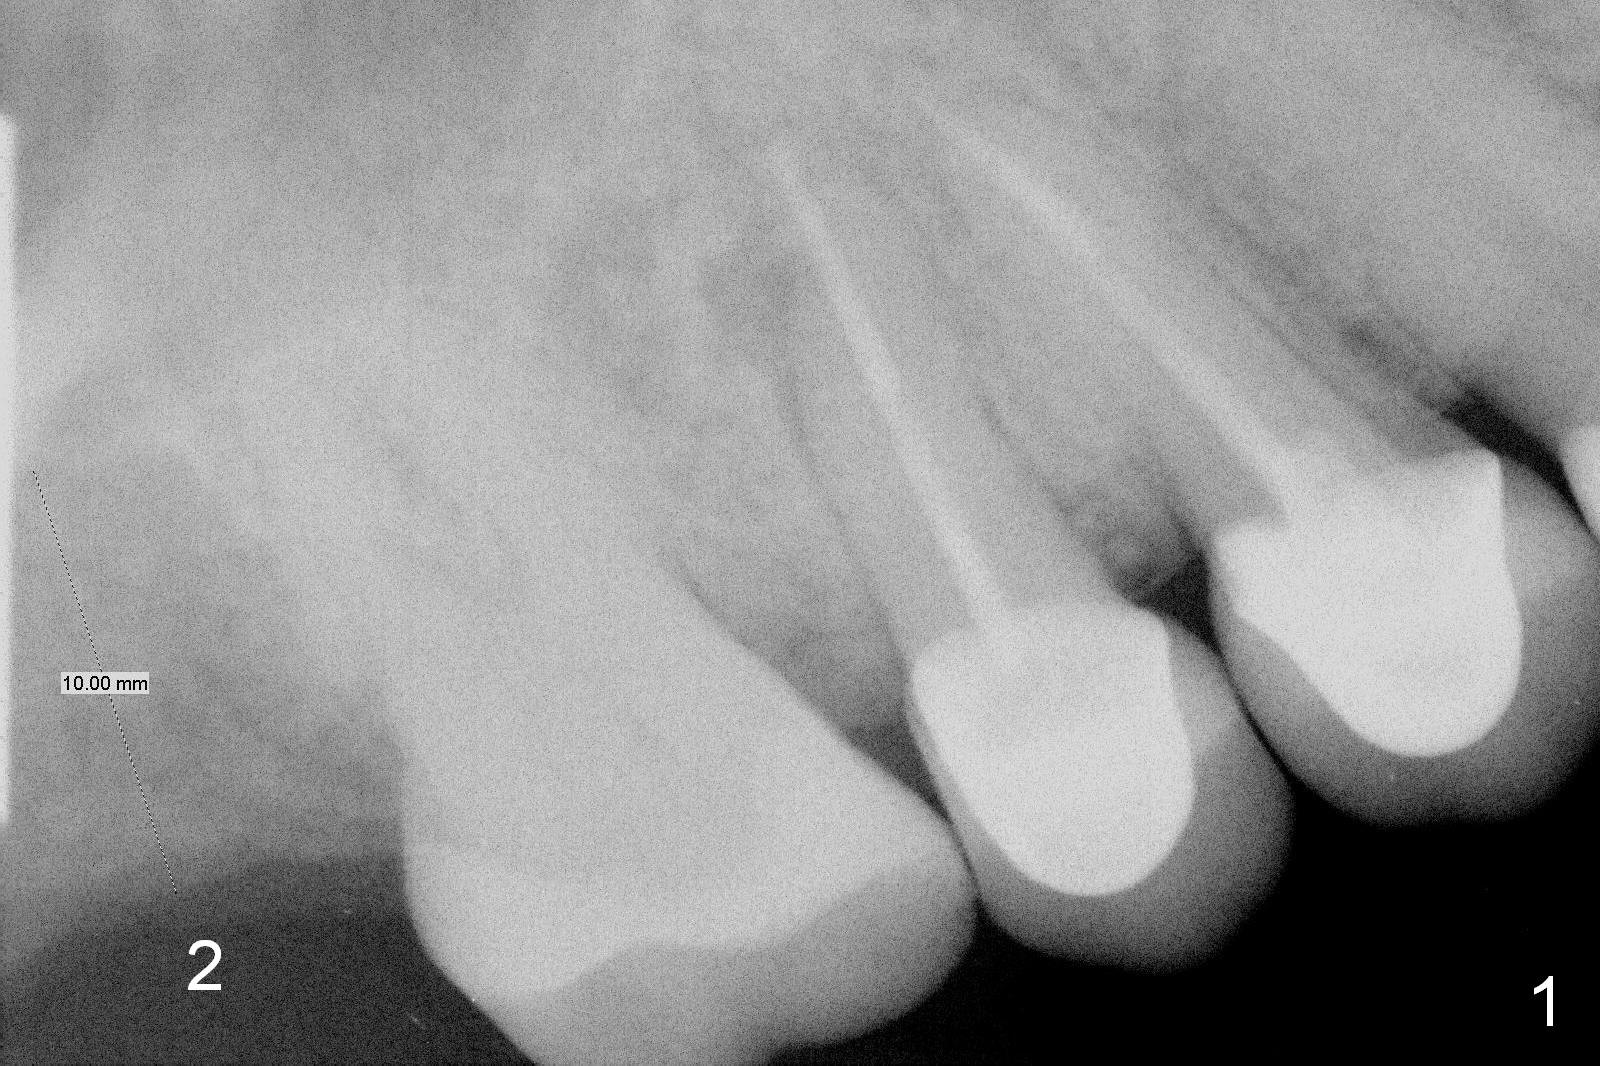

A 60-year-old woman has lost the tooth #2 for a few years (Fig.1). Since then, three of her anterior teeth have fractured and required implant placement (#8, 10,11). It appears that restoration of the tooth #2 may alleviate further anterior breakdown. There are 2 challenges associated with this case: supraeruption of the opposing teeth and low bone density (40-200).

To tackle the 1st challenge, place an implant as deep as possible and reduce the opposing tooth as early as possible (immediately after implant placement with immediate provisional if possible).